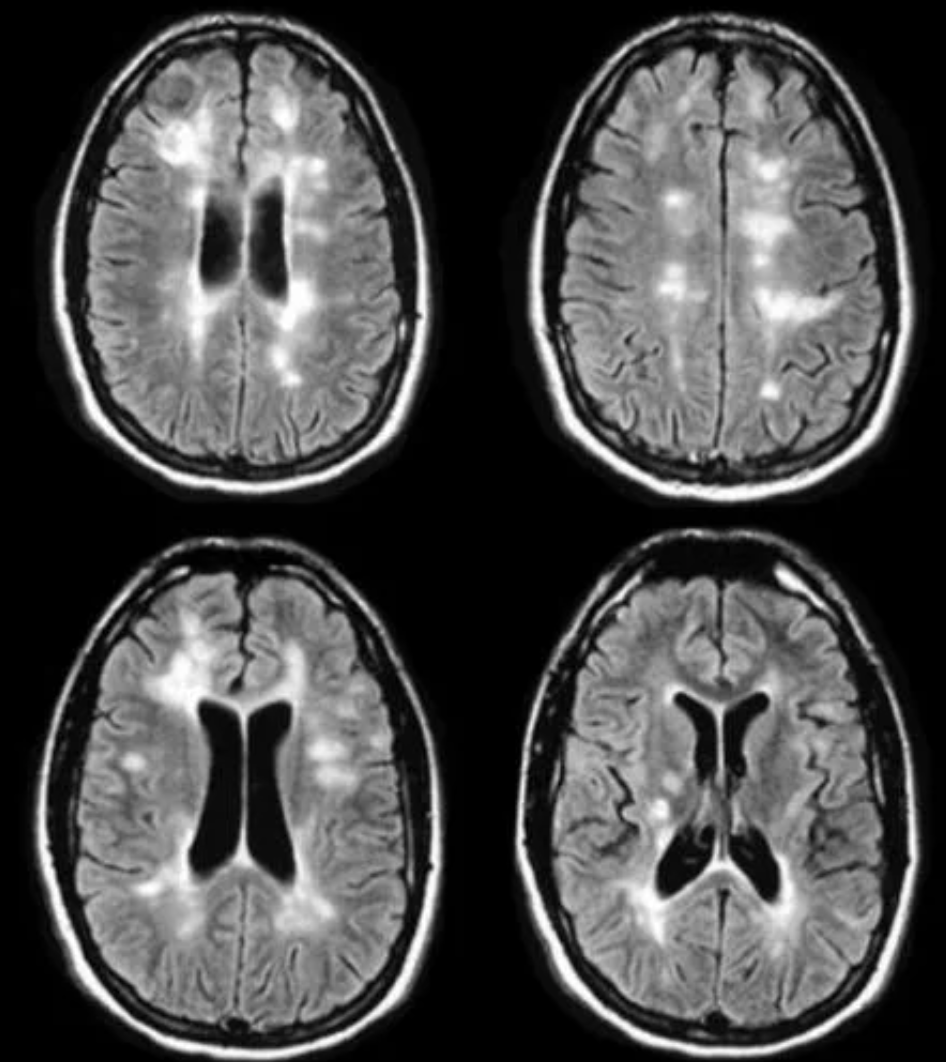

What scan do patients typically receive to identify the cause of the optic neuritis?

1 - MRI

If MS then there will be lots of white lesions